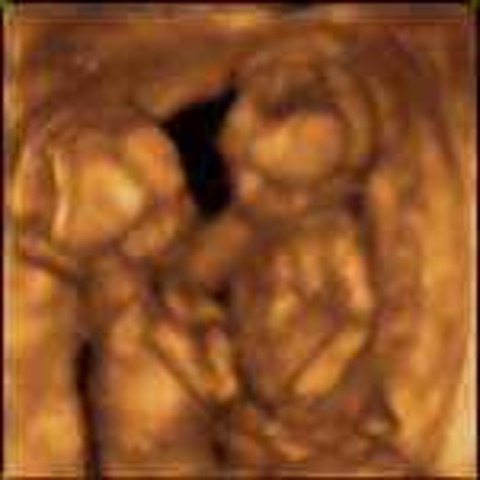

• Week 25: Exploration Continues

Week 25: Exploration Continues

The baby is mainly focused on exploring the uterus. Its sexual organs are done developing and its brain cells are starting to mature.

• Week 26: Second Trimester Ends This Week

The fetus' hands are moving a lot more and its eyes are beginning to open. The baby also weighs about 1.7 pounds at this stage. To calm itself down, the baby will suck its thumb.